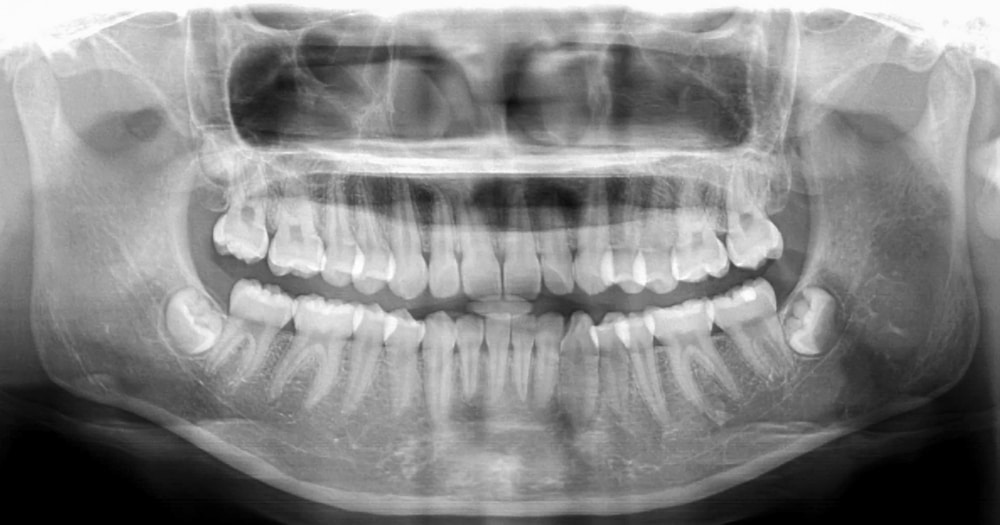

Panoramic X-Ray

A Panoramic X-ray machine rotates around your entire head to take a 360-degree view of your teeth, sinuses, and the bone structure of your head and jaws. This provides a more complete image than standard X-rays. Panoramic X-ray imagery is a valuable resource for Dr. Prewitt to use in diagnosis and treatment planning.